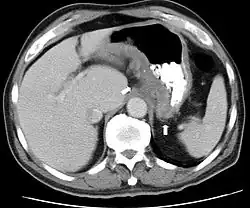

CT scan showing Crohn's disease in the fundus of the stomach -

CT and MRI scans are useful for evaluating the small bowel with enteroclysis protocols.[168] They are also useful for looking for intra-abdominal complications of Crohn's disease, such as abscesses, small bowel obstructions, or fistulae.[169] Magnetic resonance imaging (MRI) is another option for imaging the small bowel as well as looking for complications, though it is more expensive and less readily available.[170] MRI techniques such as diffusion-weighted imaging and high-resolution imaging are more sensitive in detecting ulceration and inflammation compared to CT.[171][172]